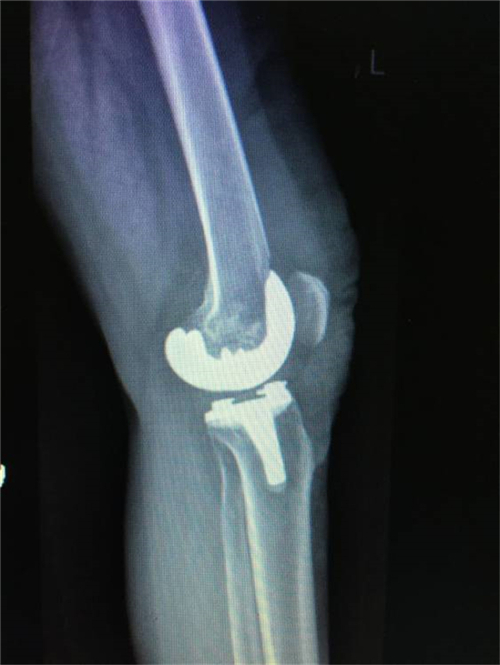

术后X线

经过与家属的耐心沟通,谭宜昌主任及其团队决定为谢某实施膝关节置换手术。8月25 日上午,谭主任及其团队历时90分钟,成功为患者实施了膝关节置换术。术后患者的膝关节畸形矫正,膝关节稳定性也已恢复,膝关节功能明显改善。出院时谢某脸上洋溢着满意的笑容,说非常感谢谭主任团队把折磨自己多年的疾病给治好了。